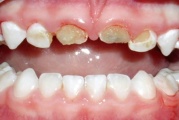

Tetratsükliini liigtarbimise tõttu värvunud hambad

Fluoroos

Fluoroosi

Hammaste defektid